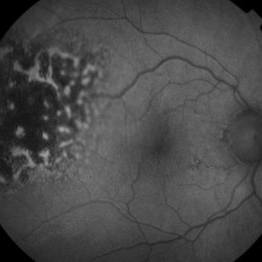

Hyper-autofluorescence of Orange Pigment Overlying a Lesion Suspicious for a Choroidal Melanoma

Hyper-autofluorescence of Orange Pigment Overlying a Lesion Suspicious for a Choroidal Melanoma

Jan 16 2019 by John S. King, MD

76-year-old white male saw his eye doctor with a three week complaint of photopsias and a shadow in his vision. Found to have a 10.5/12.5/2.5 (medium reflectivity) pigmented, choroidal mass associated with SRF and orange pigment (hyper-autofluorescence of lipofuscin, see image), and without drusen or halo.

Photographer: Stacey Coleman

Imaging device: Topcon 50

Condition/keywords: lipofuscin, orange pigment